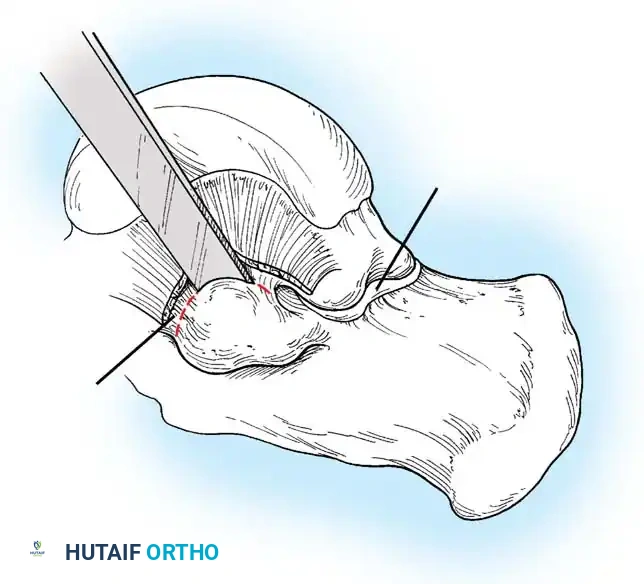

جراحة إزالة التحام الكاحل والعقب

تُجرى هذه العملية عادة للمرضى الأصغر سناً (10 إلى 15 عاماً) عندما يكون الالتحام في المفصل الأوسط (Middle Facet) صغيراً (أقل من 50% من مساحة المفصل) ولا توجد علامات على خشونة المفاصل.

يتم الدخول جراحياً من الجهة الداخلية للقدم، ويتم استئصال الجسر العظمي بدقة باستخدام أدوات دقيقة حتى يظهر الغضروف السليم للمفصل. كما هو الحال في الالتحام السابق، يتم وضع نسيج دهني أو شمع عظمي لمنع الالتصاق مجدداً.